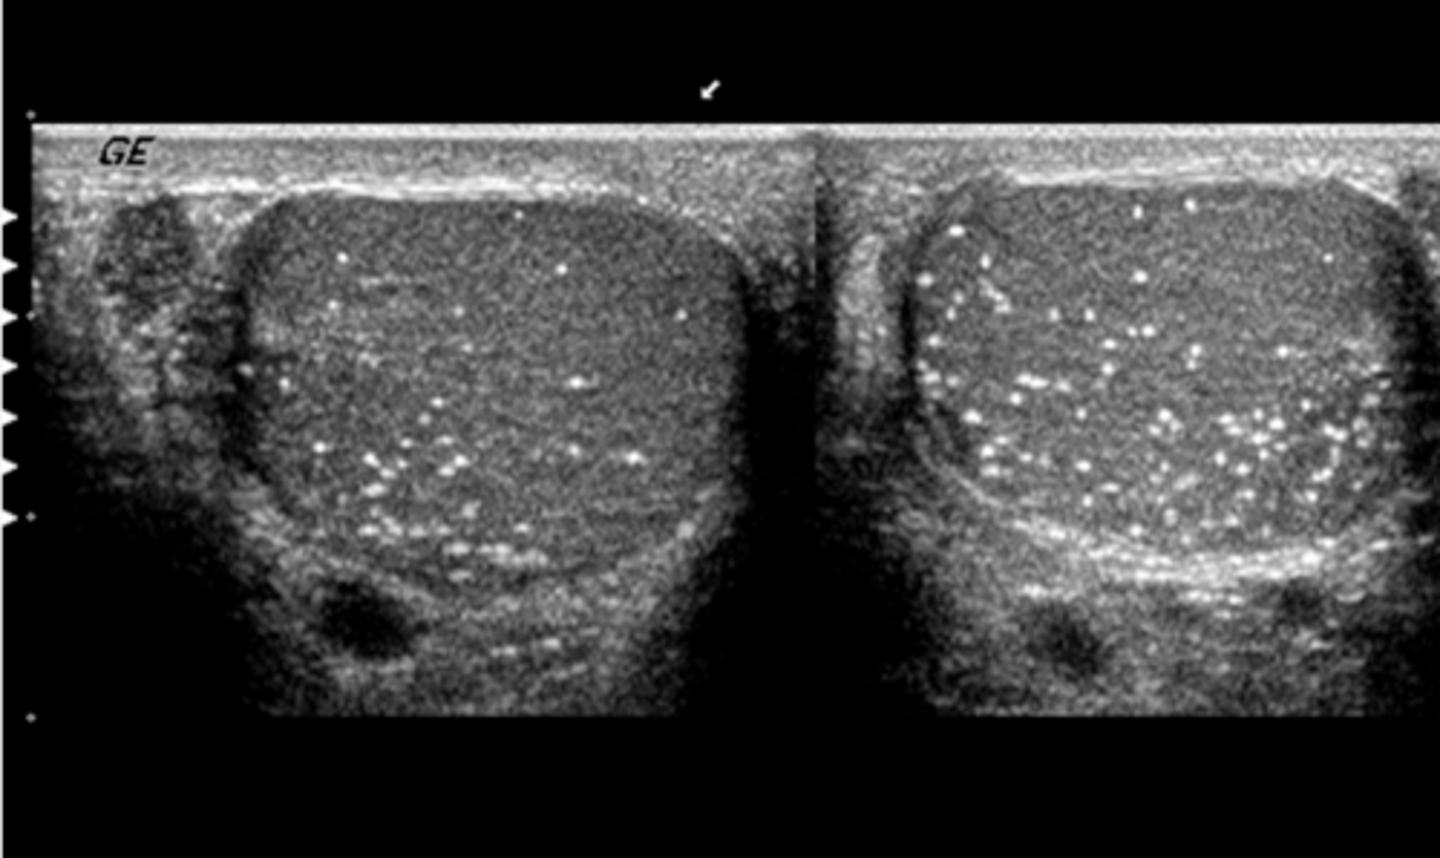

c. microlithiasis

What pathology is present in this image?

a. spermatocele

b. seminoma

d. metastatic disease

e. orchitis